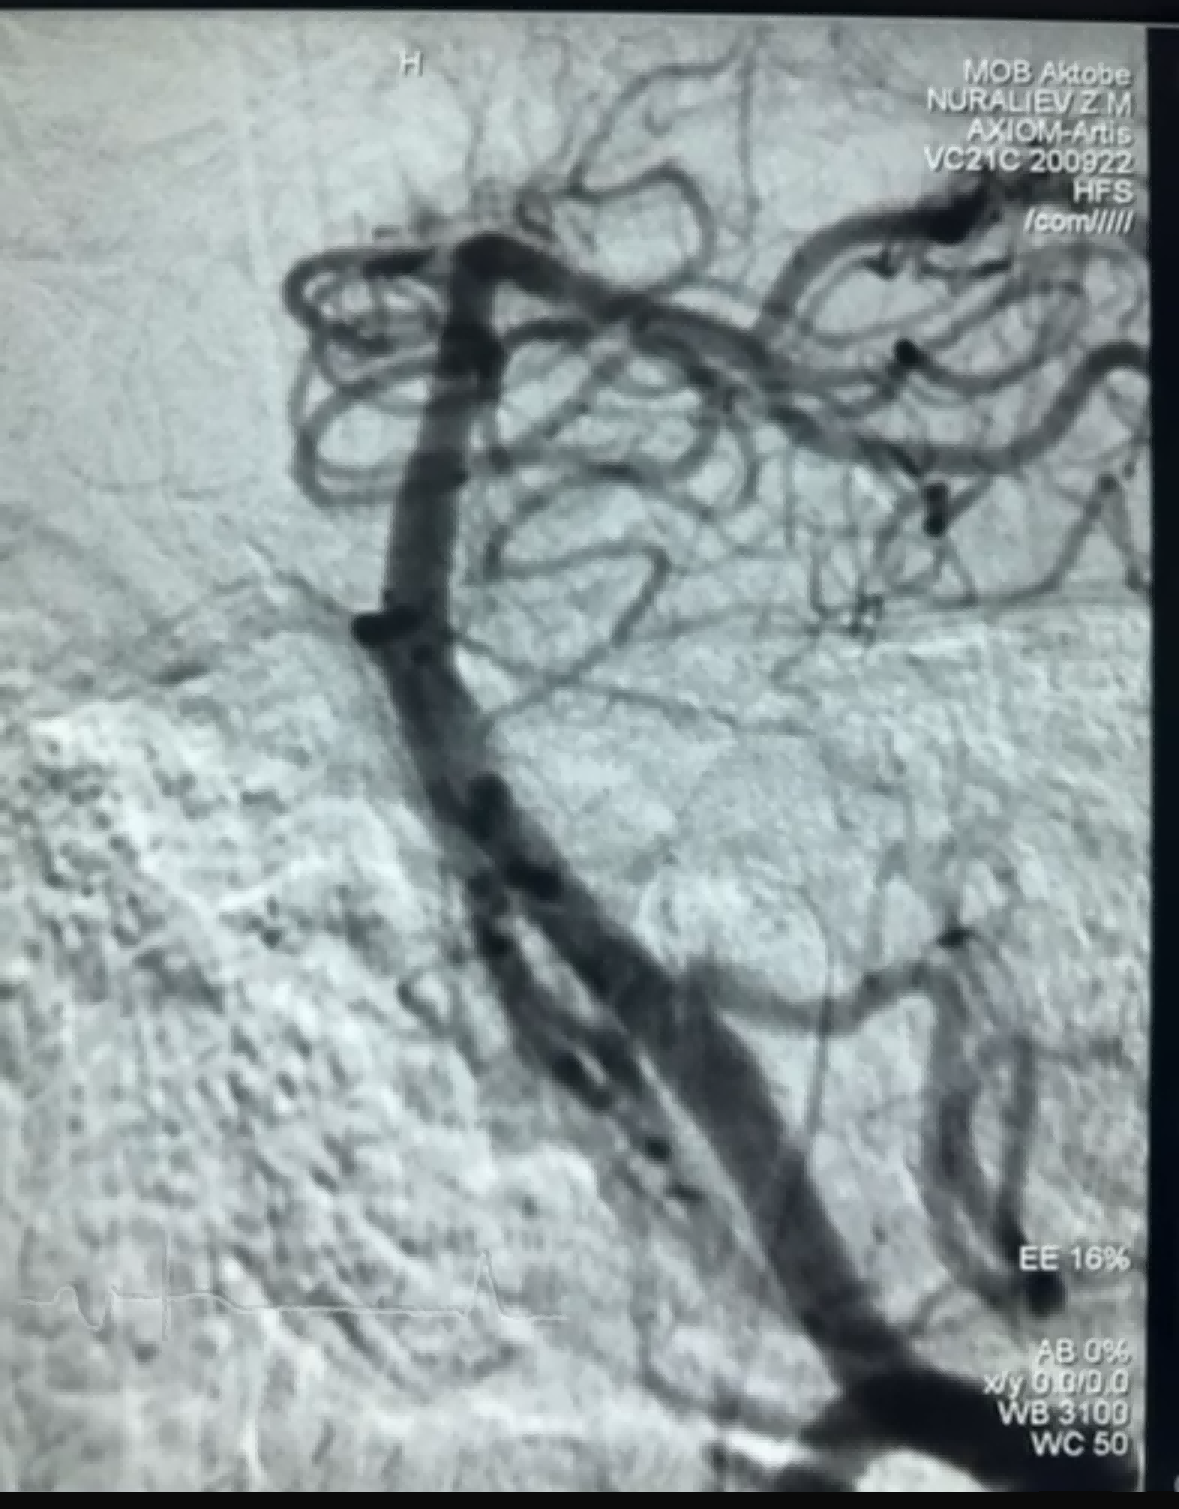

For nylig var der et vellykket trombektomitilfælde med Dredger Stent Retriever fra NeuroSafe Medical Co., Ltd. Dredger Stent Retriever har en ikke-invasiv blød spids, som i høj grad reducerer risikoen for intimal skade, og har et unikt specialformet hul design, der fanger blodpropper hovedsageligt ved at fastspænde mellemrumsændringerne.